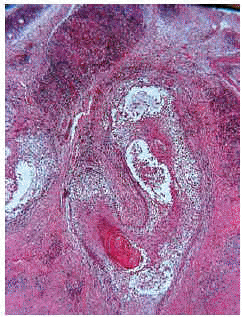

Las formas de mucinosis folicular primaria localizada y de mucinosis folicular primaria difusa fueron similares histológicamente. Se caracterizaron por abundantes depósitos de mucina en el folículo y una intensa destrucción folicular (figs. 6 y 7), que en ocasiones se acompañaba de granulomas foliculares secundarios. El infiltrado inflamatorio era escaso, de distribución superficial y perifolicular, sin atipias ni epidermotropismo. Los eosinófilos fueron escasos o ausentes en el infiltrado.

Fig. 7.--Depósitos de mucina marcados con hierro coloidal.